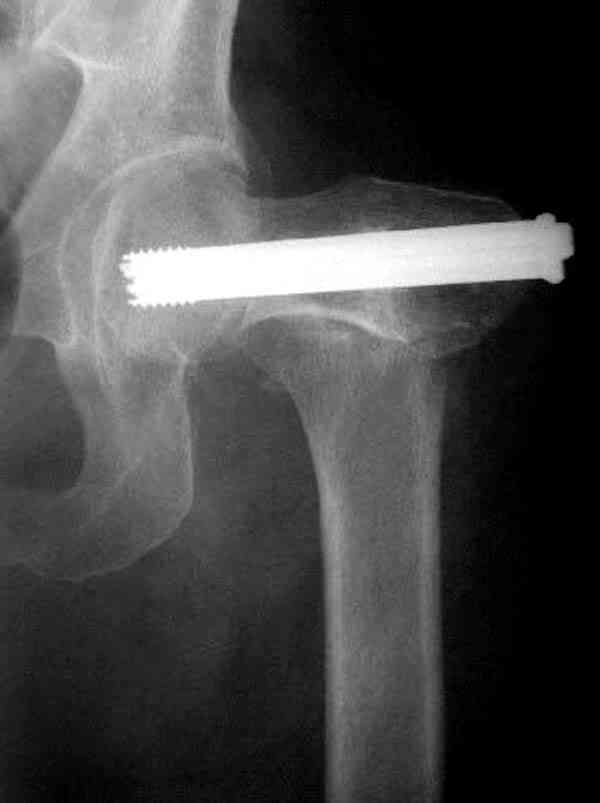

На Московской конференции в ноябре была продемонстрирована удивительная методика профилактического армирования шейки бедра у пациенток с остеопорозом и переломом контрлатеральной шейки в анамнезе.Странно, но дискуссии это сообщение не вызвало.Кто что думает об этом?

Спасибо, Антон. Я автор того сообщения по профилактическому армированию шейки бедренной кости, которое прозвучало на конференции, посвященной 50-летию создания АО. Мне тоже хотелось услышать вопросы по теме. Мы травматологи-ортопеды в первую очередь хирурги, а не терапевты. Почему в вопросе профилактики и лечения остеопороза мы ограничиваемся только консервативными методами лечения? Как можно практически научить больного не получать травмы, когда немало случаев возникновения переломов даже в постели. Первоначально идея армирования ШБК многих, при ком я озвучивал ее, шокировала, затем возникала дискуссия и большинство поддерживали эту идею. Мне бы очень хотелось развернуть дискуссию на странице этого сайта.

Кликните для загрузки файла P3230006.JPG

54KB (56062 bytes)

Уважаемый Антон! У меня было всего три клинических наблюдения, снимки были продемонстрированы на московской конференции. Количества этих снимков хватило для подачи заявки, а затем и получения патента на изобретение. В свое время РОСПАТЕНТ потребовал подтверждения методики клиническими наблюдениями. У одной из больных действительно произошла повторная травма, и произошел подвертельный перелом на стороне армированной шейки бедренной кости (см. снимки). Это подтвердило основную идею изобретения - была сохранена и головка, и армированная шейка бедренной кости. Но тут не обошлось безпроблем. Анестезиологи отказались давать наркоз, а провести остеосинтез под м/а пластиной и винтом DHS не согласилась больная. Дальнейшее лечение скелетным вытяжением. На контр. Рентгенограмме через 2 месяца признаки формирования костной мозоли. Повторных обращений двух других пациентов не было. Для более детальных исследований и выводов необходимо значительно большее количество клинических наблюдений. Такие исследования могли быть проведены в условиях клиник медуниверситета. Напомню, я работаю в травмотделении провинциальной городской больницы. Насчет экспертов страховых компаний, так пусть они выскажут свое мнение. Армирование кости - это плановые операции по желанию больного, какие здесь могут быть противоречия? На армирование все больные, к моему удивлению, согласились довольно легко и сразу, поэтому остеосинтез и армирование были проведены в течение одной операции. С уважением А.М.